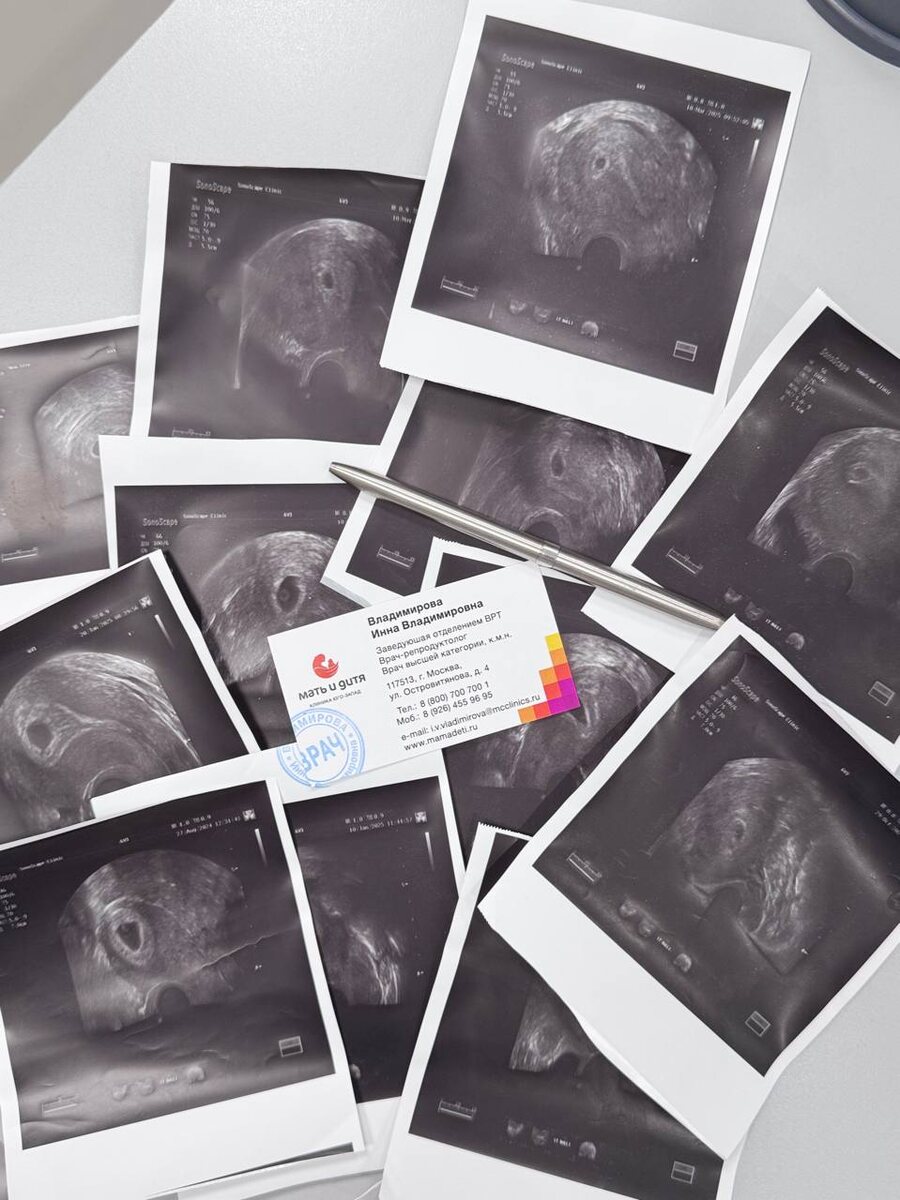

Репродуктолог Владимирова Инна

Хороших выходных